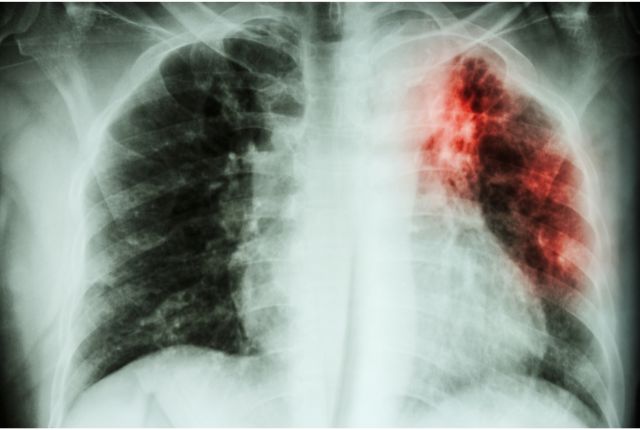

Fibrose pulmonaire traitement naturel: Qu’est-ce que la fibrose pulmonaire ?La fibrose pulmonaire est une maladie chronique qui se caractérise par la cicatrisation progressive du tissu pulmonaire. Cette transformation affecte l’élasticité des poumons et réduit leur capacité à assurer une bonne oxygénation du sang. Le patient ressent alors une difficulté croissante à respirer, pouvant évoluer vers une insuffisance respiratoire.

Avec le temps, cette affection limite fortement les activités physiques, entraîne une fatigue persistante et altère la qualité de vie. Bien qu’il n’existe pas encore de traitement curatif, une prise en charge naturelle bien pensée peut atténuer les symptômes et ralentir l’évolution de la maladie.